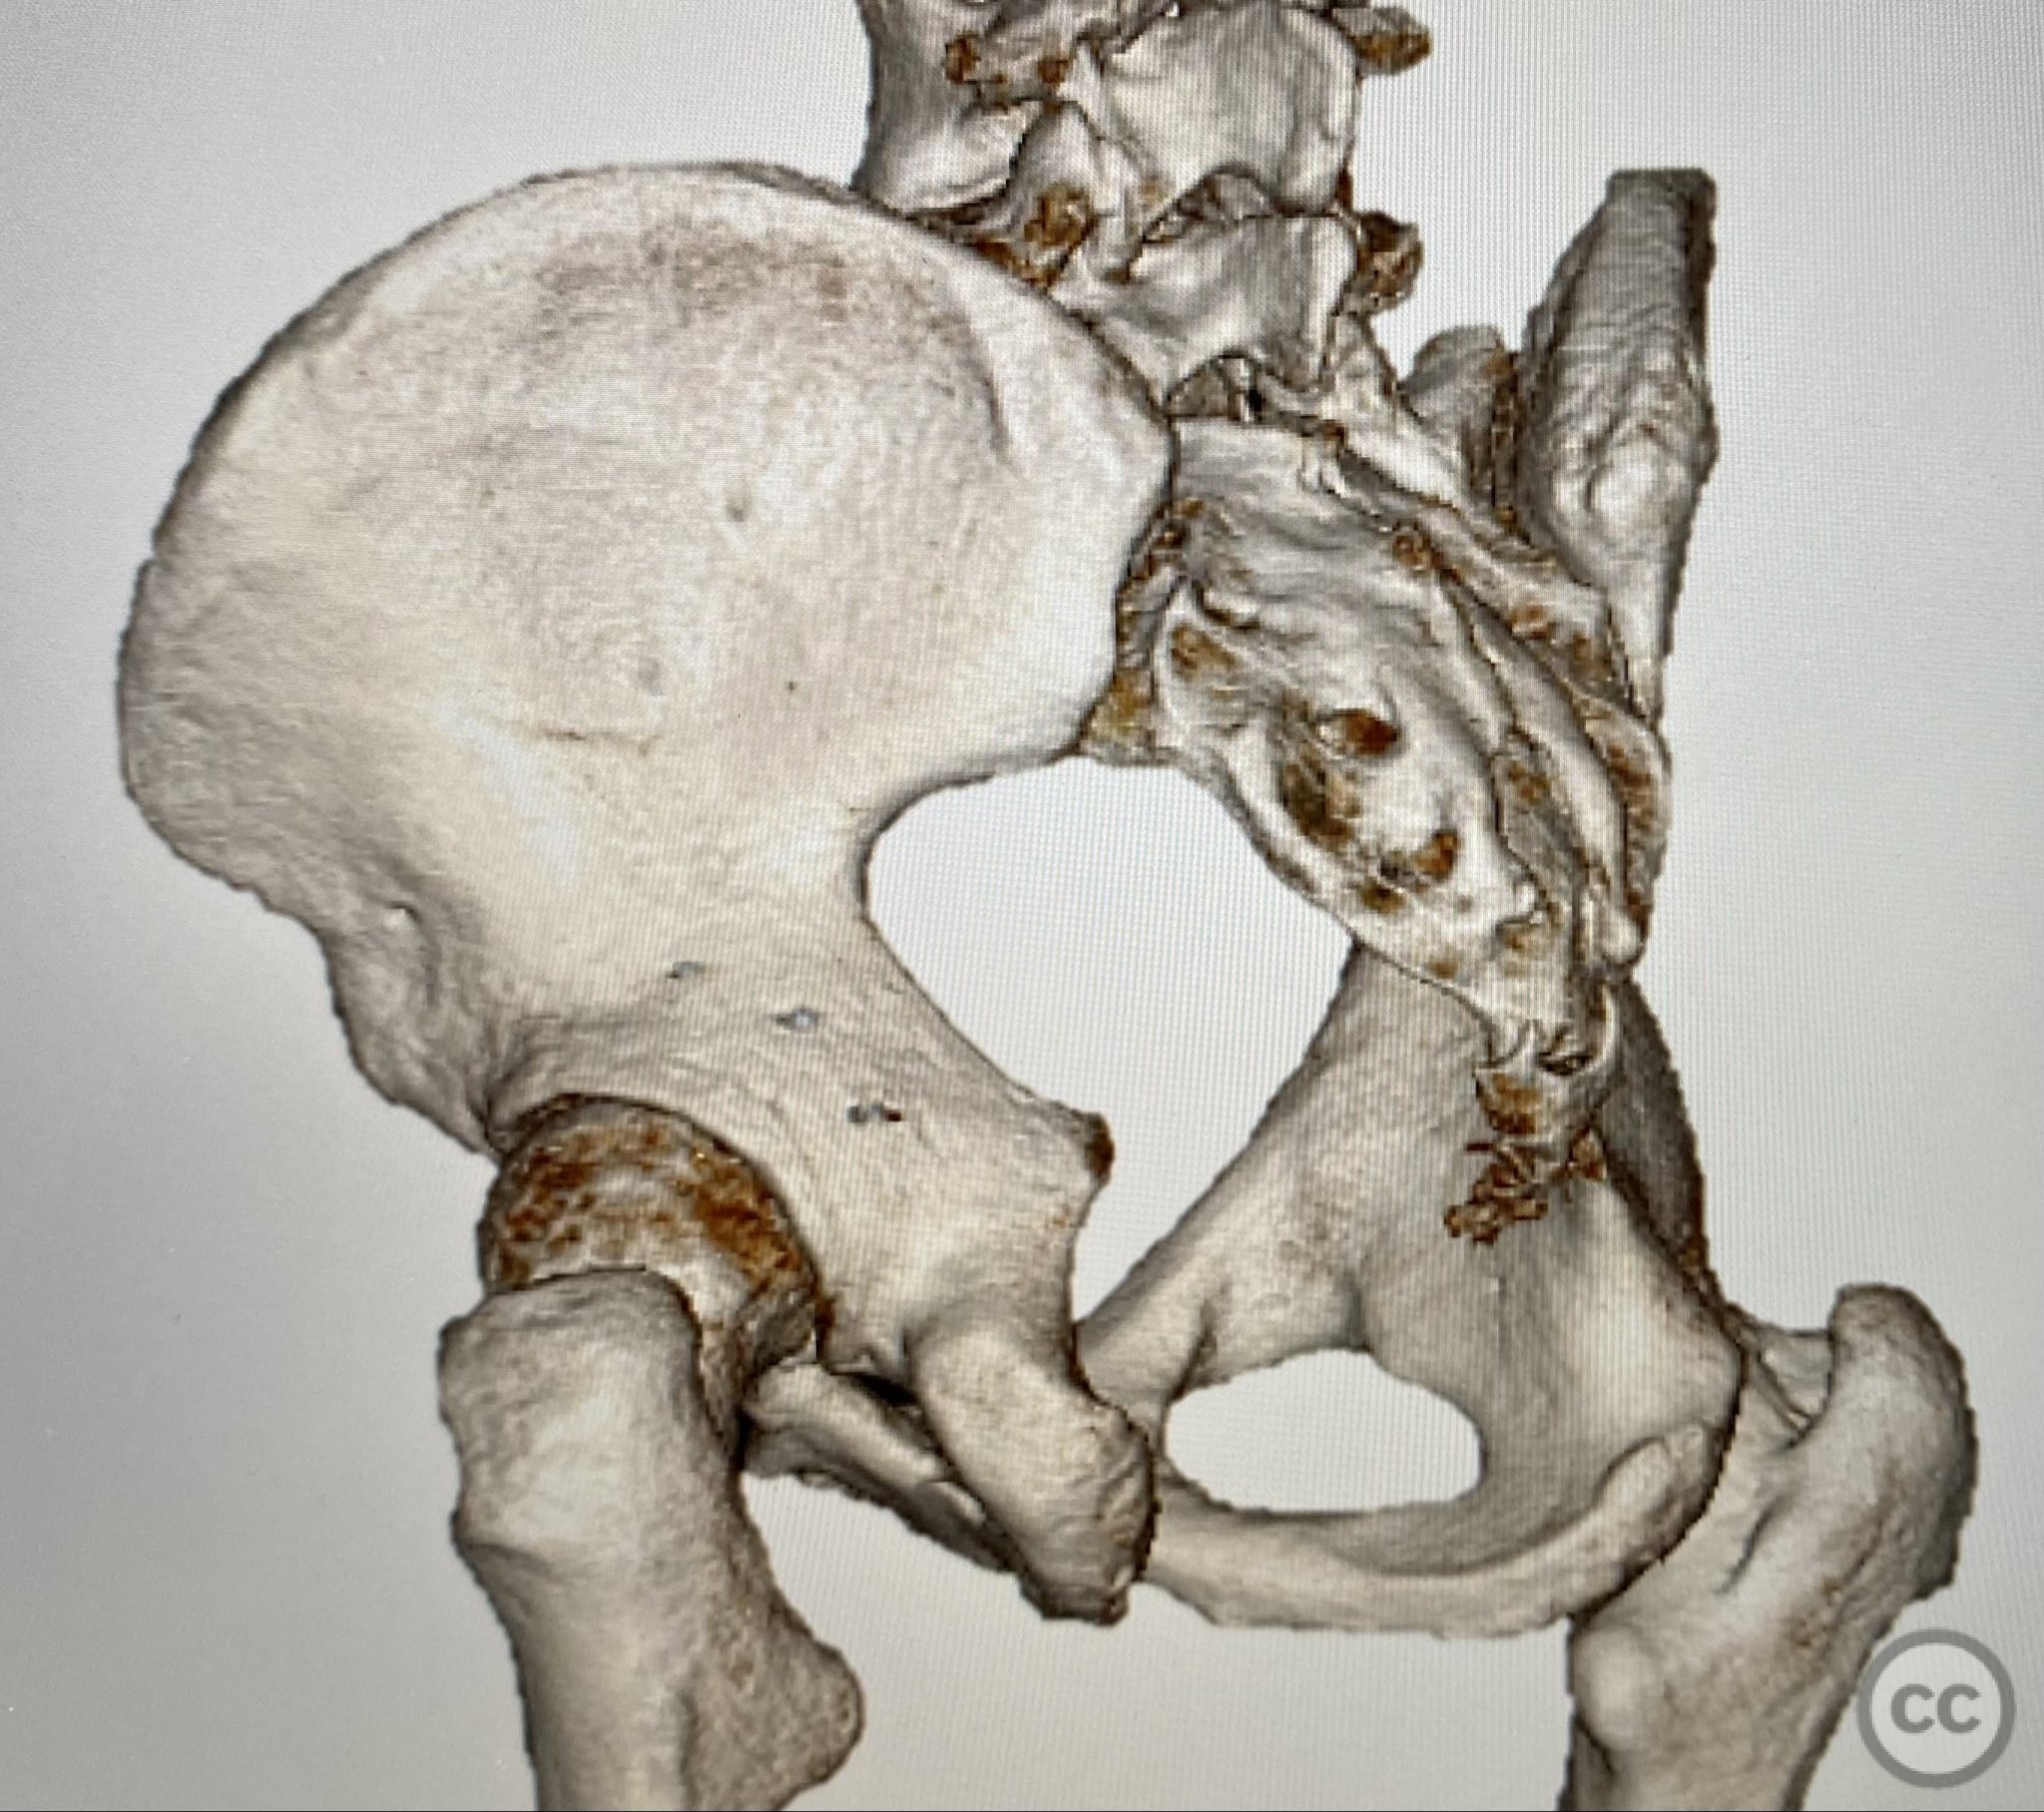

Clinical and radiological findings:  A patient involved in a motor vehicle collision presented with left hip pain exacerbated by any attempted movement. Initial axial and surface-rendered computed tomography (CT) imaging demonstrated an essentially nondisplaced posterior wall (PW) acetabular fracture (AO/OTA 62-A1.1). However, the anteroposterior (AP) scan image and coronal reconstructions revealed significant hip joint asymmetry. Examination under anesthesia with fluoroscopic guidance confirmed persistent joint incongruity, with the femoral head subluxating posteriorly at 50–60 degrees of flexion. A pure chondral fragment was identified as being interposed between the femoral head and the intact region of the posterior wall, accounting for the clinical and radiological asymmetry.

Intraoperatively, persistent hip joint asymmetry was noted on fluoroscopic imaging, correlating with preoperative findings. The femoral head exhibited posterior subluxation at moderate flexion angles due to mechanical obstruction by a pure chondral fragment wedged between the femoral head and posterior wall. Removal of this fragment restored joint congruity and symmetry. The posterior wall fracture, though minimally displaced, was deemed unstable based on intraoperative assessment and fluoroscopic stress testing. The fragment’s capsular attachment facilitated stabilization using suture anchor repair. The use of a Kocher-Langenbeck approach was considered essential for adequate exposure, reduction, and stabilization; arthroscopic techniques were not employed.